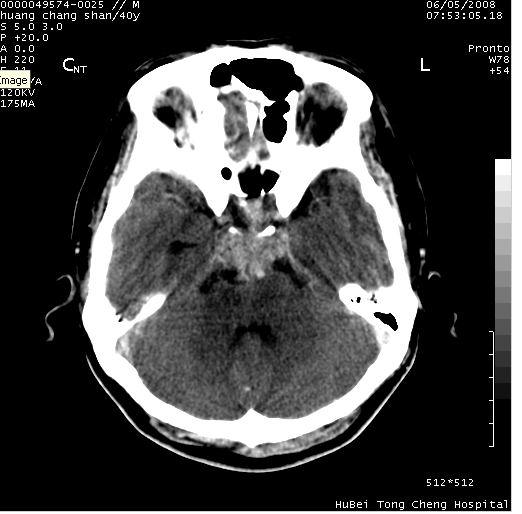

患者 m,40y。头痛,视力模糊,多饮多尿,性欲减退半年余。

行ct平扫+增强,图象如下:

肿瘤强化明显、鞍部骨质结构未见增大、破坏,考虑脑膜瘤可能性大

鞍背无破坏和明显受压,病变明显均匀强化,边界清晰。鞍上区脑膜瘤可能性大,不除外生殖细胞瘤。

平扫病灶呈等密度,增强后强化明显,均匀一致,结合病史首先考虑:垂体瘤。脑膜瘤不支持,因为脑膜瘤平扫多为实性呈均匀高密度影像,内分泌症状多不明显,垂体内分泌素测定正常。

鞍上池肿瘤,鞍背及垂体窝形态变化不明显,病灶强化密度均匀且高度强化,考虑实性颅咽管瘤、生殖细胞瘤及脑膜瘤可能。

结合临床考虑鞍上生殖细胞瘤可能性大于脑膜瘤(增强未见脑膜围征),建议结合冠状位扫描看病灶起源及垂体窝、鞍底情况。垂体窝内未见明显软组织密度影,垂体窝未见扩大,暂不考虑垂体瘤;病灶较大,未见囊变及钙化,颅咽管瘤不支持。期待结果!

2、ct表现:肿瘤呈类圆形,均匀略高密度,无囊变,无钙化。侧脑室有扩大。

4、鉴别诊断:脑膜瘤,瘤体内点状钙化最具特征性,常位于鞍结节。颅咽管瘤,蛋壳样钙化,常有囊变。动脉瘤,位于鞍旁,强化与动脉一致。有时尚需与发生于鞍区的生殖细胞瘤鉴别,生殖细胞瘤钙化亦较常见。